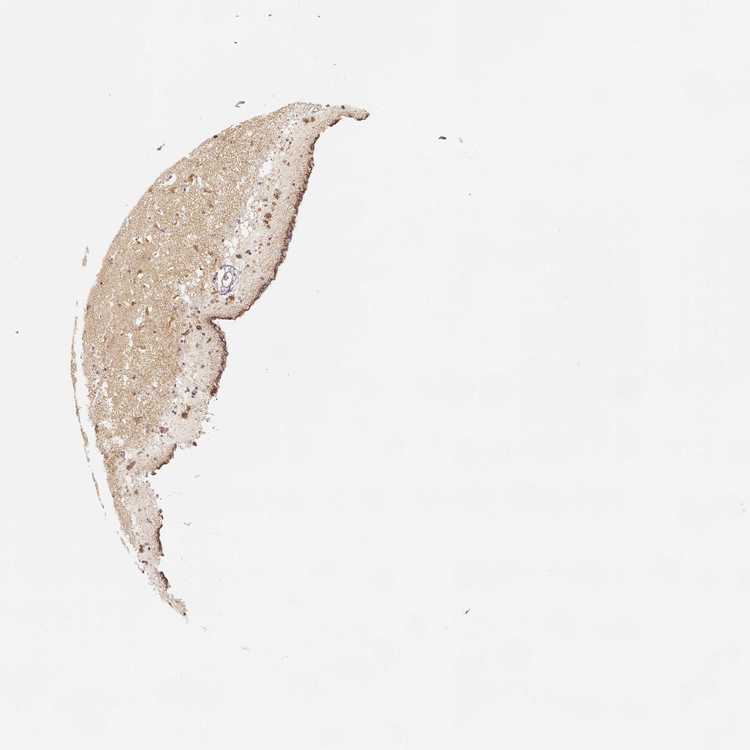

TISSUE PRIMARY DATA CAUDATE Show tissue menu

Caudate

CAUDATE - Antibody stainingi

Antibody staining in the annotated cell types in the current human tissue is reported as not detected, low, medium, or high, based on conventional immunohistochemistry profiling in selected tissues. This score is based on the combination of the staining intensity and fraction of stained cells.

Each image is clickable and will lead to virtual microscopy that enables deeper exploration of all samples and also displays staining intensity scores, fraction scores and subcellular localization as well as patient and tissue information for each sample.

Antibody HPA036978Antibody HPA036979Antibody CAB068215

Glial cells MediumLowLow

Neuronal cells MediumLowMedium